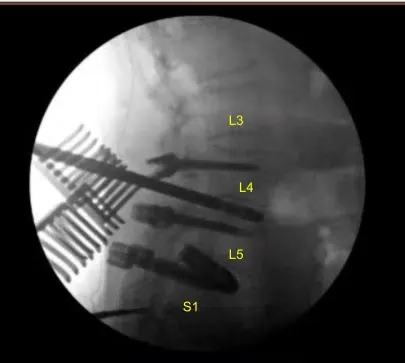

Los tornillos pediculares restantes a la izquierda en L4 y bilateral en L5 fueron reemplazados por nuevos tornillos pediculares ligeramente ampliados. Se logró una solución más ajustada. A continuación, colocamos los nuevos tornillos pediculares en L3, decorticando bilateralmente con un taladro eléctrico de alta velocidad, canulando con localizador pedicular navegado, palpando para detectar brechas, midiendo la profundidad, subroscando 1 mm y colocando los tornillos pediculares de forma habitual sin dificultad. Las señales de neuromonitorización se mantuvieron estables.

A continuación, se realizó un TAC intraoperatorio que mostró la posición correcta de todos los tornillos. A continuación, realizamos una laminectomía L3-4 utilizando rongeurs de Leksell que recogieron autoinjertos para morselización en caso de artrodesis, exponiendo un ligamento flavo hipertrófico que fue retraído de forma fragmentada con rongeurs de Kerrison.

Las heridas estaban completamente irrigadas. Se seleccionaron varillas de titanio precortadas y predelineadas y se colocaron bilateralmente sobre los tulipanes desde L3 hasta L5, asegurándose con tapas de bloqueo que se apretaron finalmente con un dispositivo de par y antitorque.